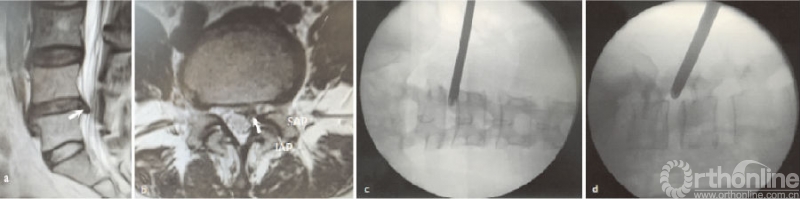

后外侧区突出是最常见的腰椎间盘突出症类型,其突出区域在于侧隐窝及椎弓根区(见图2a-b)。基于行走根的解剖位置,单纯的椎弓根区一般不引起症状;但在侧隐窝区,即使大米粒状的突出,都可以引起相对剧烈的下肢放射痛。

常规的TESSYS穿刺技术可置入工作通道(见图2a-b),手术的难点在于寻找神经根腹侧突出的椎间盘。由于腰椎椎体多呈中间低两边高的肾型,侧隐窝区的突出建议在寻找突出椎间盘时,先用工作通道舌面切除小部分凸起的椎体后上角,以充分显露椎弓根内侧区域,在摘除突出间盘后,即可清晰看到神经根腹侧及搏动情况,减少残留可能。

(a)(b)L4/5节段后外侧区突出的矢状位和横断位;(c)(d)工作通道放置X线透视图;↖指突出椎间盘,IAP指下关节突,SAP指上关节突

图2 MRI示L4/5节段后外侧椎间盘突出及置管图